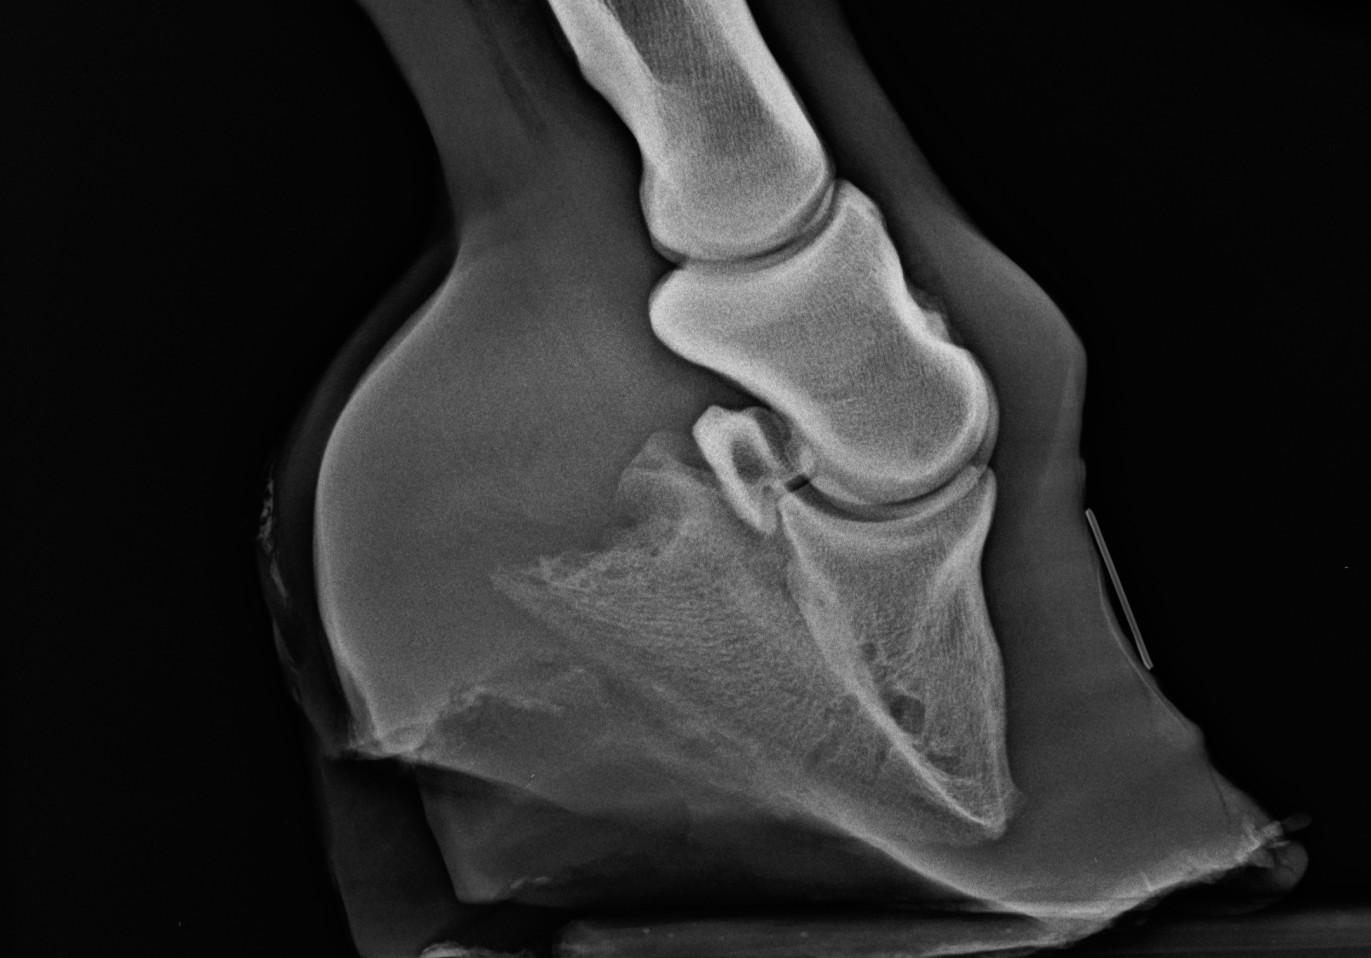

A diagnózis nem nehéz, de RTG vizsgálatot szoktunk végezni.

Felnőtt, bakpatás ló. Gyűrött, torzult hegyfali szaru - ezt lehet elérni feszítő patkókkal. A patacsont hegye lekerekedett a nyomástól. Ezt a lovat műteni kellett volna fiatal korában.